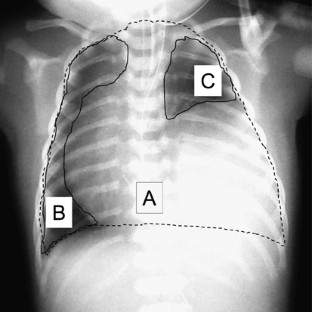

Congenital diaphragmatic hernia (CDH) has a poor prognosis, despite intensive management. The prognosis of CDH is correlated with hypoplastic lung, but it is difficult to measure the degree of hypoplasia. The aims of this study were, therefore, to examine the relationship between chest X-ray and prognosis, and to assess whether the radiographic findings were a good indicator of hypoplastic lungs in patients with CDH.

Fifty neonates with CDH were classified radiographically into apex and hilar types. To assess the differences in clinical course between these two groups, gestational age, birth weight, prenatal diagnosis, survival rate, requirement of extracorporeal membrane oxygenation (ECMO) therapy and lung area on X-rays were analyzed.

In all, 32 cases were of the apex type and 18 were hilar. The survival rate of the hilar group (33%) was significantly worse than that of the apex group (81%) (P<0.001). The hilar group required ECMO therapy more frequently than did the apex group.

The present results show a significant correlation between survival rate and the findings of chest X-rays in CDH. Radiographic findings are thus a good clinical indicator of the prognosis of CDH in neonates.